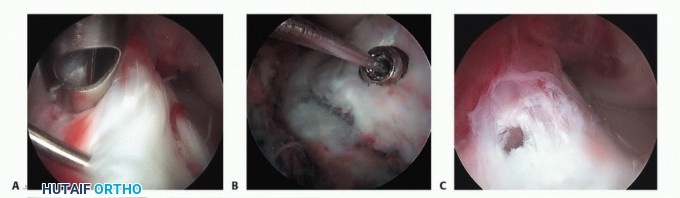

Attempt to reduce the fracture fragments as described earlier in the section “Fracture Reduction” (TECH FIG 1).

- TECH FIG 1 • A. Arthroscopic image taken of a type III tibial spine fracture. B. Arthroscopic image showing anatomic reduction of the fracture fragments.

FIG 3 • Arthroscopic view of the knee. A. A completely displaced tibial spine fracture with interposition of the intermeniscal ligament blocks reduction of the fracture. B. Probe helps remove the entrapped intermeniscal ligament to allow proper reduction of the tibial spine fracture fragment.*